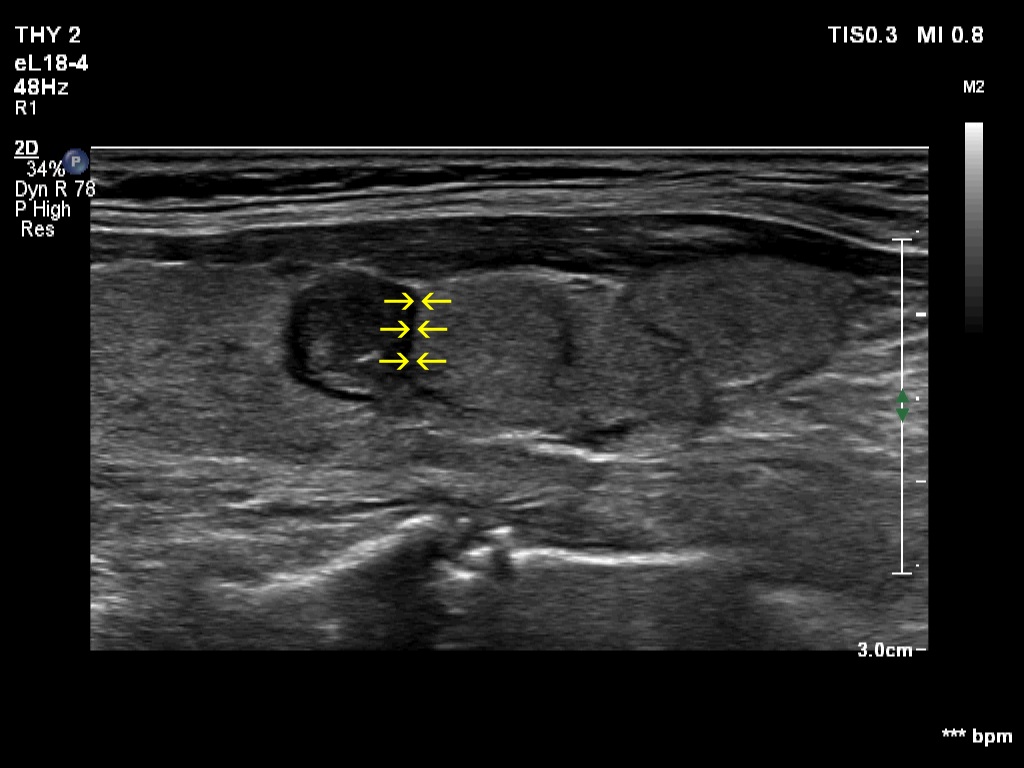

The shape of the nodule - case 2255 (ultrasonographic picture 7b)

Right lobe, longitudinal scan, enlargement. The yellow arrows point to the borders between the upper hypoechoic and the lower echonormal nodule.